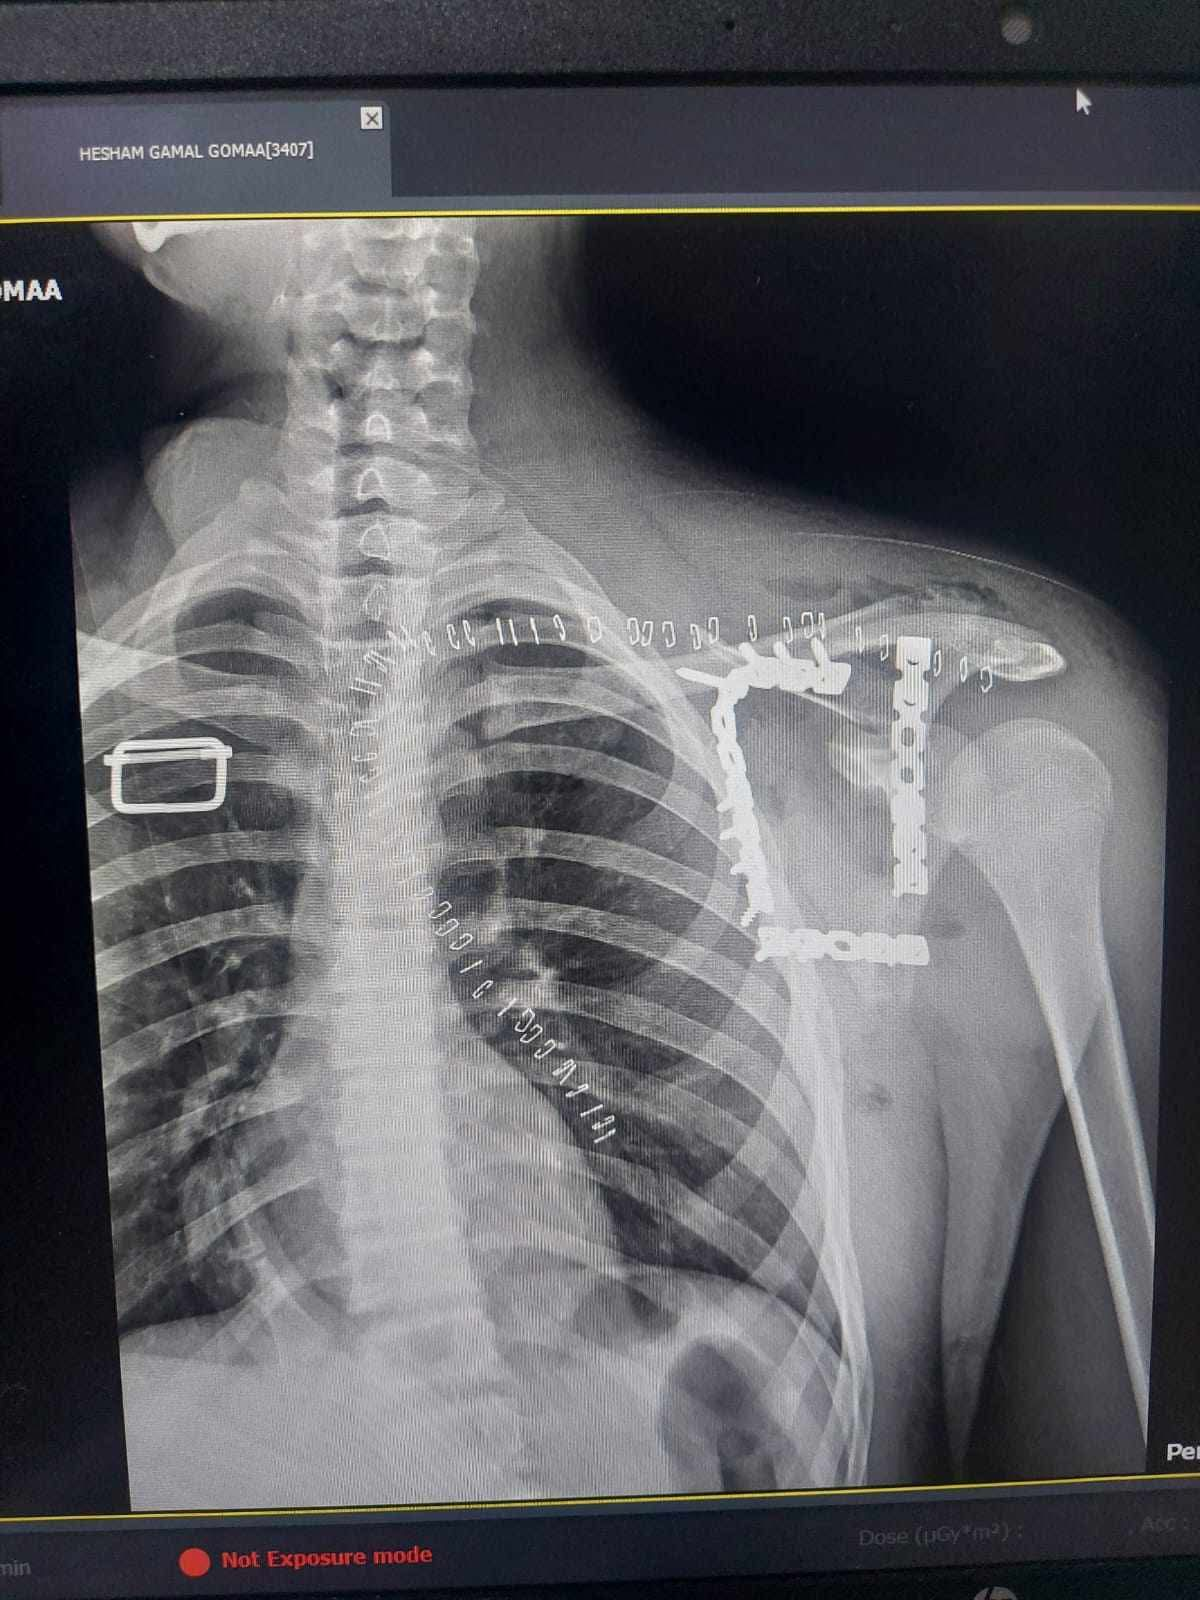

شهد مستشفى التأمين الصحي بالفيوم واقعة طبية متميزة بعد استقبال شاب يبلغ من العمر 17 عاما كان يعاني من كسر مفتت بعظمة لوح الكتف وهي من الاصابات الدقيقة والنادرة التي تحتاج الى تدخل جراحي متخصص نظرا لتعقيد موقعها وتشابكها مع العضلات والمفاصل المحيطة ما يجعل التعامل معها تحديا كبيرا امام الفرق الطبية.

خضع المريض لعملية جراحية معقدة استمرت نحو 4 ساعات تحت تأثير التخدير العام حيث قام الفريق الطبي برد وتثبيت الكسر باستخدام الشرائح والمسامير في اجراء دقيق يتطلب مهارة عالية وخبرة كبيرة خاصة في هذا النوع من الاصابات النادرة.

العملية مرت بنجاح دون حدوث مضاعفات وتمكن الاطباء من تثبيت العظمة بشكل سليم يساعد على استعادة المريض لوظائف الكتف تدريجيا خلال فترة العلاج.

تعد هذه الجراحة الاولى من نوعها داخل محافظة الفيوم وهو ما يعكس مدى التطور الذي تشهده مستشفيات التأمين الصحي من حيث الامكانيات والكفاءات الطبية القادرة على التعامل مع الحالات الحرجة والمعقدة